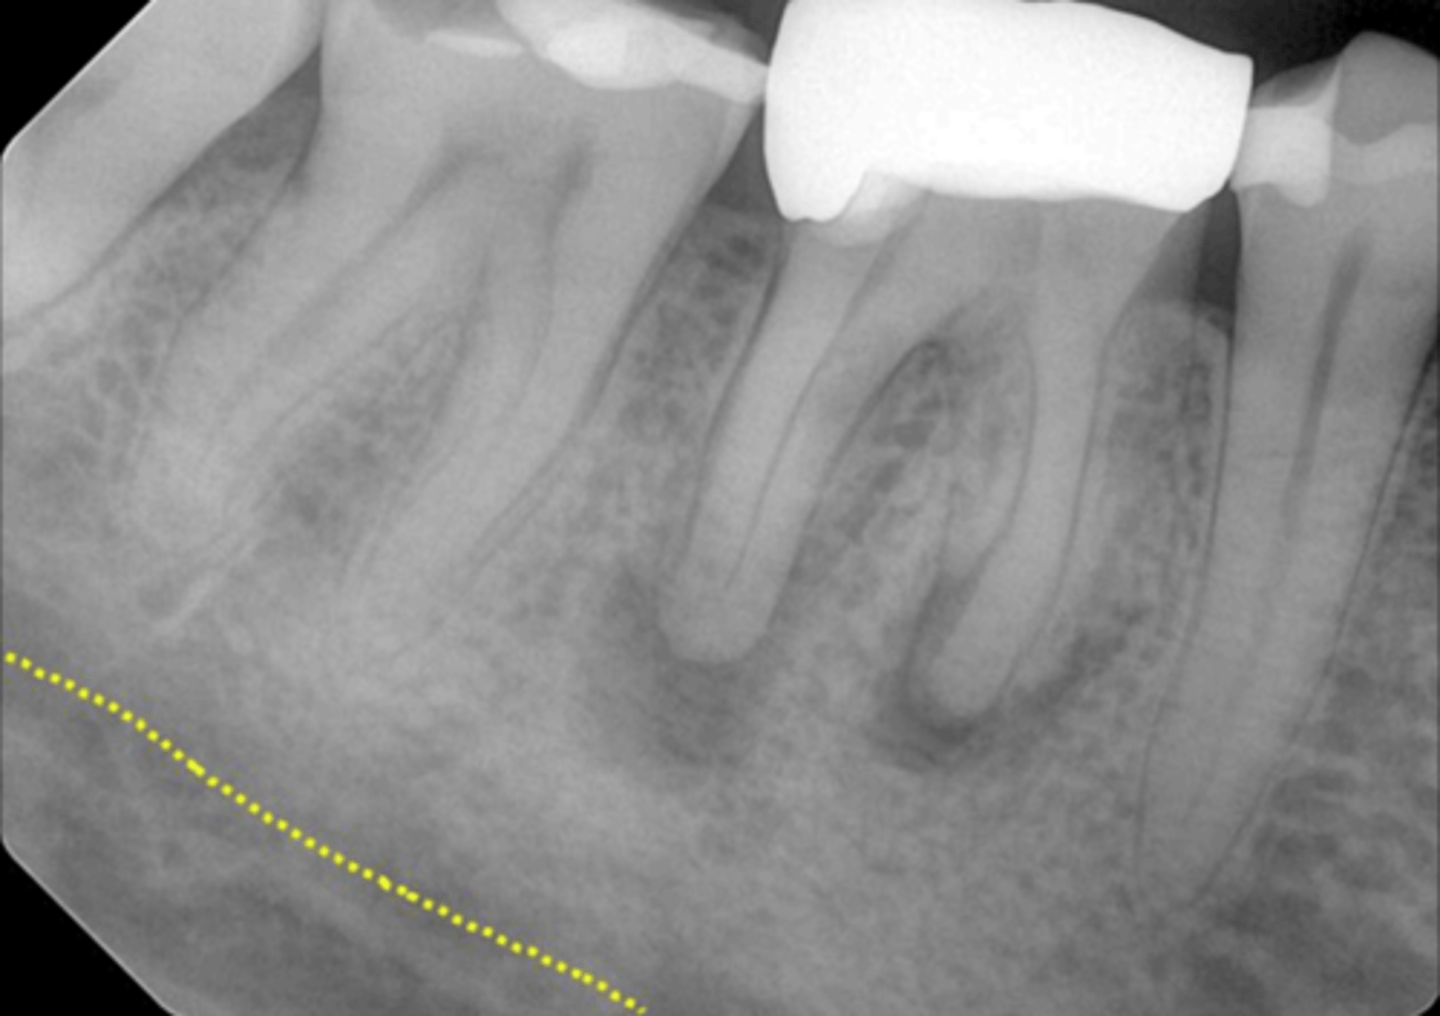

Mandibular canal

What is causing the thick radiolucent line surrounding the dotted line?

External oblique ridge

What is indicated by the dotted line?